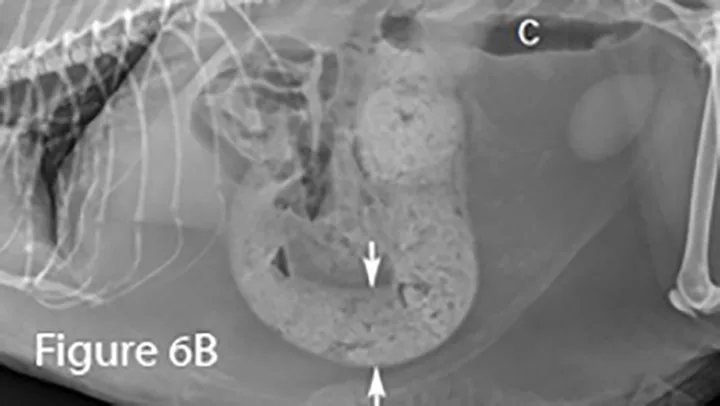

Lateral (Figure 6B) and ventrodorsal (Figure 6C) abdominal radiographs of severely distended segment of bowel identified sonographically and properly diagnosed as severe small intestinal obstruction (arrows). Of note, there is fecal-like material in the small intestine. An ileocecocolic mass was diagnosed during exploratory laparotomy. This mass was apparently obscured by gas during ultrasound examination. (C = colon)